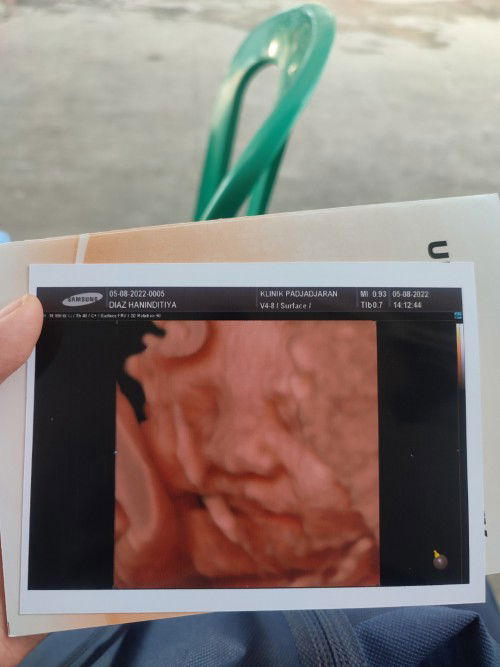

USG di UK 32W

Kontrol dan USG di UK 32W tgl 5 Agustus 2022 kemarin agak sedih ya. Gimana enggak, sebelumnya USG di UK 26W dd baby sehat tanpa ada permasalahan apapun, tapi USG kali ini sedih bgt dd baby dinyatakan masih posisi sungsang kepala diatas dan bokong dibawah dengan adanya 1x lilitan tali pusar di lehernya. Sekarang lagi istiqomah melakukan saran dokter untuk sering sujud nungging insyaallah akan membantu dd baby pindah posisi dan lilitan di lehernya terlepas. Ada yg punya pengalaman yg serupa kah mom? Semangat kita pejuang mommy first new born, semoga Allah mempermudah langkah kita apapun itu.